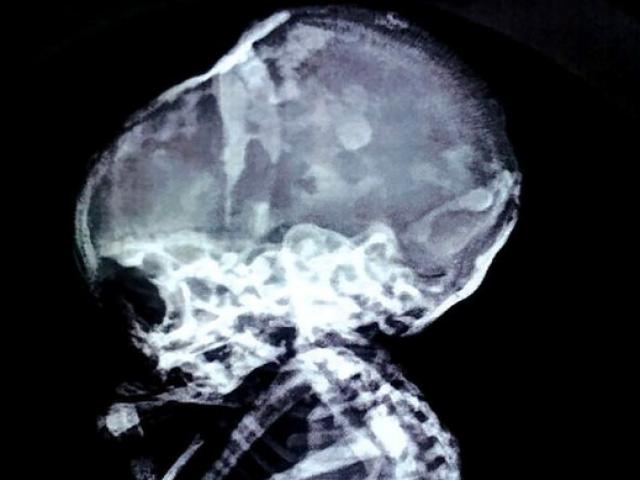

Cái chai sau khi được lấy ra khỏi bụng nạn nhân và hình chụp X-quang trước đó. Ảnh: Shanghaiist

Người đàn ông 60 tuổi này nói rằng do quá ngứa mông nên ông đã đẩy cái chai vào khá sâu và không ngờ khiến nó chui tọt vào bên trong. Hình ảnh chụp X-quang cho thấy cái chai đang nằm bên trong cơ thể người đàn ông với phần đầu đầu vươn gần tới ruột. Bác sĩ Lin, người điều trị cho bệnh nhân, nói với các phóng viên rằng ông có thể cảm thấy cái chai khi chạm vào bụng người đàn ông. Sau một cha phẫu thuật, bác sĩ Lin đã lấy thành công cái chai ra khỏi trực tràng của người đàn ông. Cũng không rõ sau đó cơn ngứa của người đàn ông có thuyên giảm hay không.